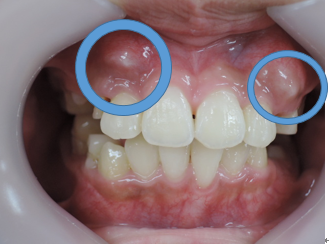

よく診る、難しい症例(奥歯の隙間)